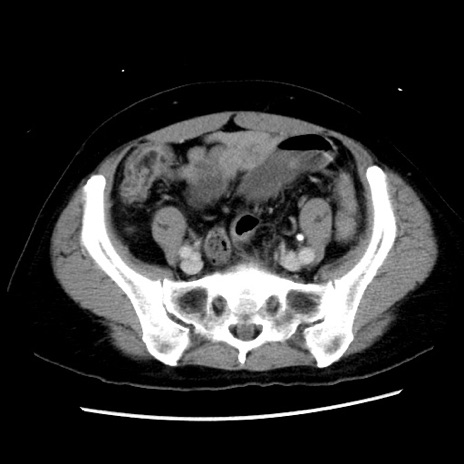

症例10(横断像)

【症例】 50歳代女性

【主訴】 腹痛

【現病歴】前日生レバーを食べた。今朝に排便あり。 昼前に突然発症の腹痛を生じ、当院救急外来を受診した。

【既往歴】 子宮筋腫にてで子宮全摘後

【身体所見】 意識清明、腹部:平坦、軟、下腹部やや左を中心に圧痛・反跳痛あり、筋性防御あり

【データ】WBC 7800、CRP 0.07